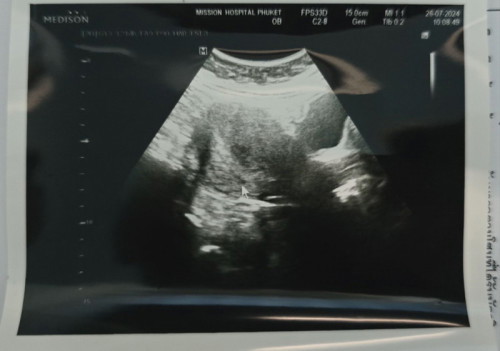

4w 5D ไม่เจอถุงตั้งครรภ์

รบกวนสอบถามประสบการณ์แม่ๆนะคะ ซาวด์หน้าท้องยังไม่เจอถุงตั้งครรรภ์ 3 ข้อสันนิษฐานของคุณหมอบอกว่า 1. อายุครรภ์ยังน้อยอยู่ 2.ท้องลม 3. ท้องนอกมดลูก อีก 2 สัปดาห์นัดซาวด์ใหม่อีกครั้ง แอบจิตตกค่ะ แม่ๆคนไหนที่ตั้งครรภ์สำเร็จแล้วเคยเป็นแบบนี้บ้างคะ ช่วยแชร์ประสบการณ์หน่อยค่ะ